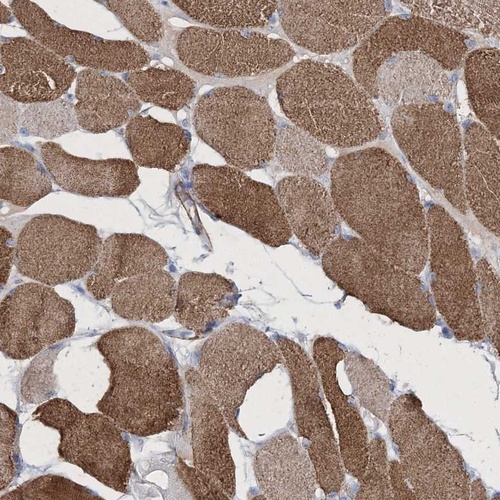

Immunohistochemical staining of human skeletal muscle shows moderate cytoplasmic positivity in myocytes.